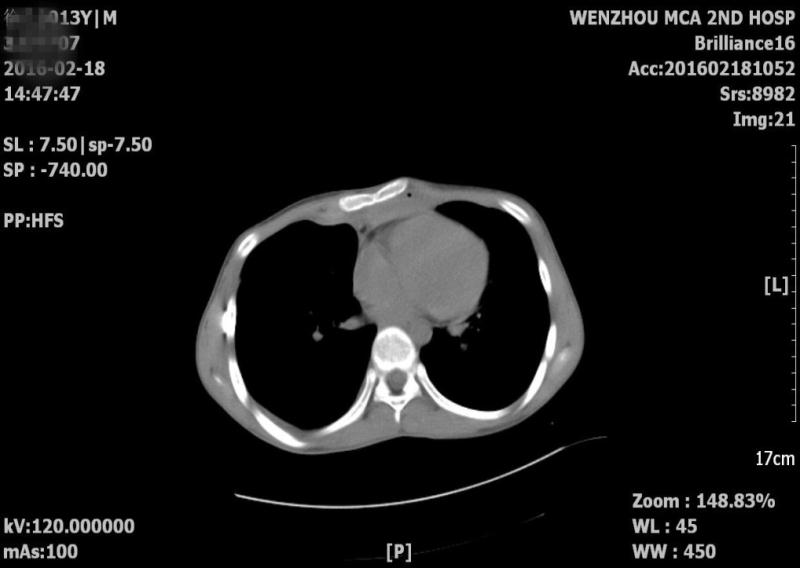

先天性漏斗胸患者目前的手术方法是需要在前后胸壁间植入钢板撑起胸骨,但由于小康的情况较为特殊,留给医生操作的空间十分有限,又加上心脏紧贴胸骨,手术操作时极易伤及心脏,这也成为摆在医生面前的一道难题。我院心胸外科胡型锑主任和赵琦峰主任对小康的病情进行了全面细致的评估和分析,在充分考虑手术难度及危险因素的基础上,决定在常规两侧胸开切口外,再在最凹陷处再增加一个切口,而这个切口是给术者用手牵拉胸板留出空隙,再用手慢慢引导钢板穿过空隙所用,这对术者的经验和手法的要求非常之高。手术由胡型锑主任主刀,平时只用30-40分钟完成的手术,这次大概用了近一个小时的时间完成。术后小康气促情况明显好转,再经过一段时间的修整,小康就可以和其他孩子一样,享受运动带来的乐趣了。